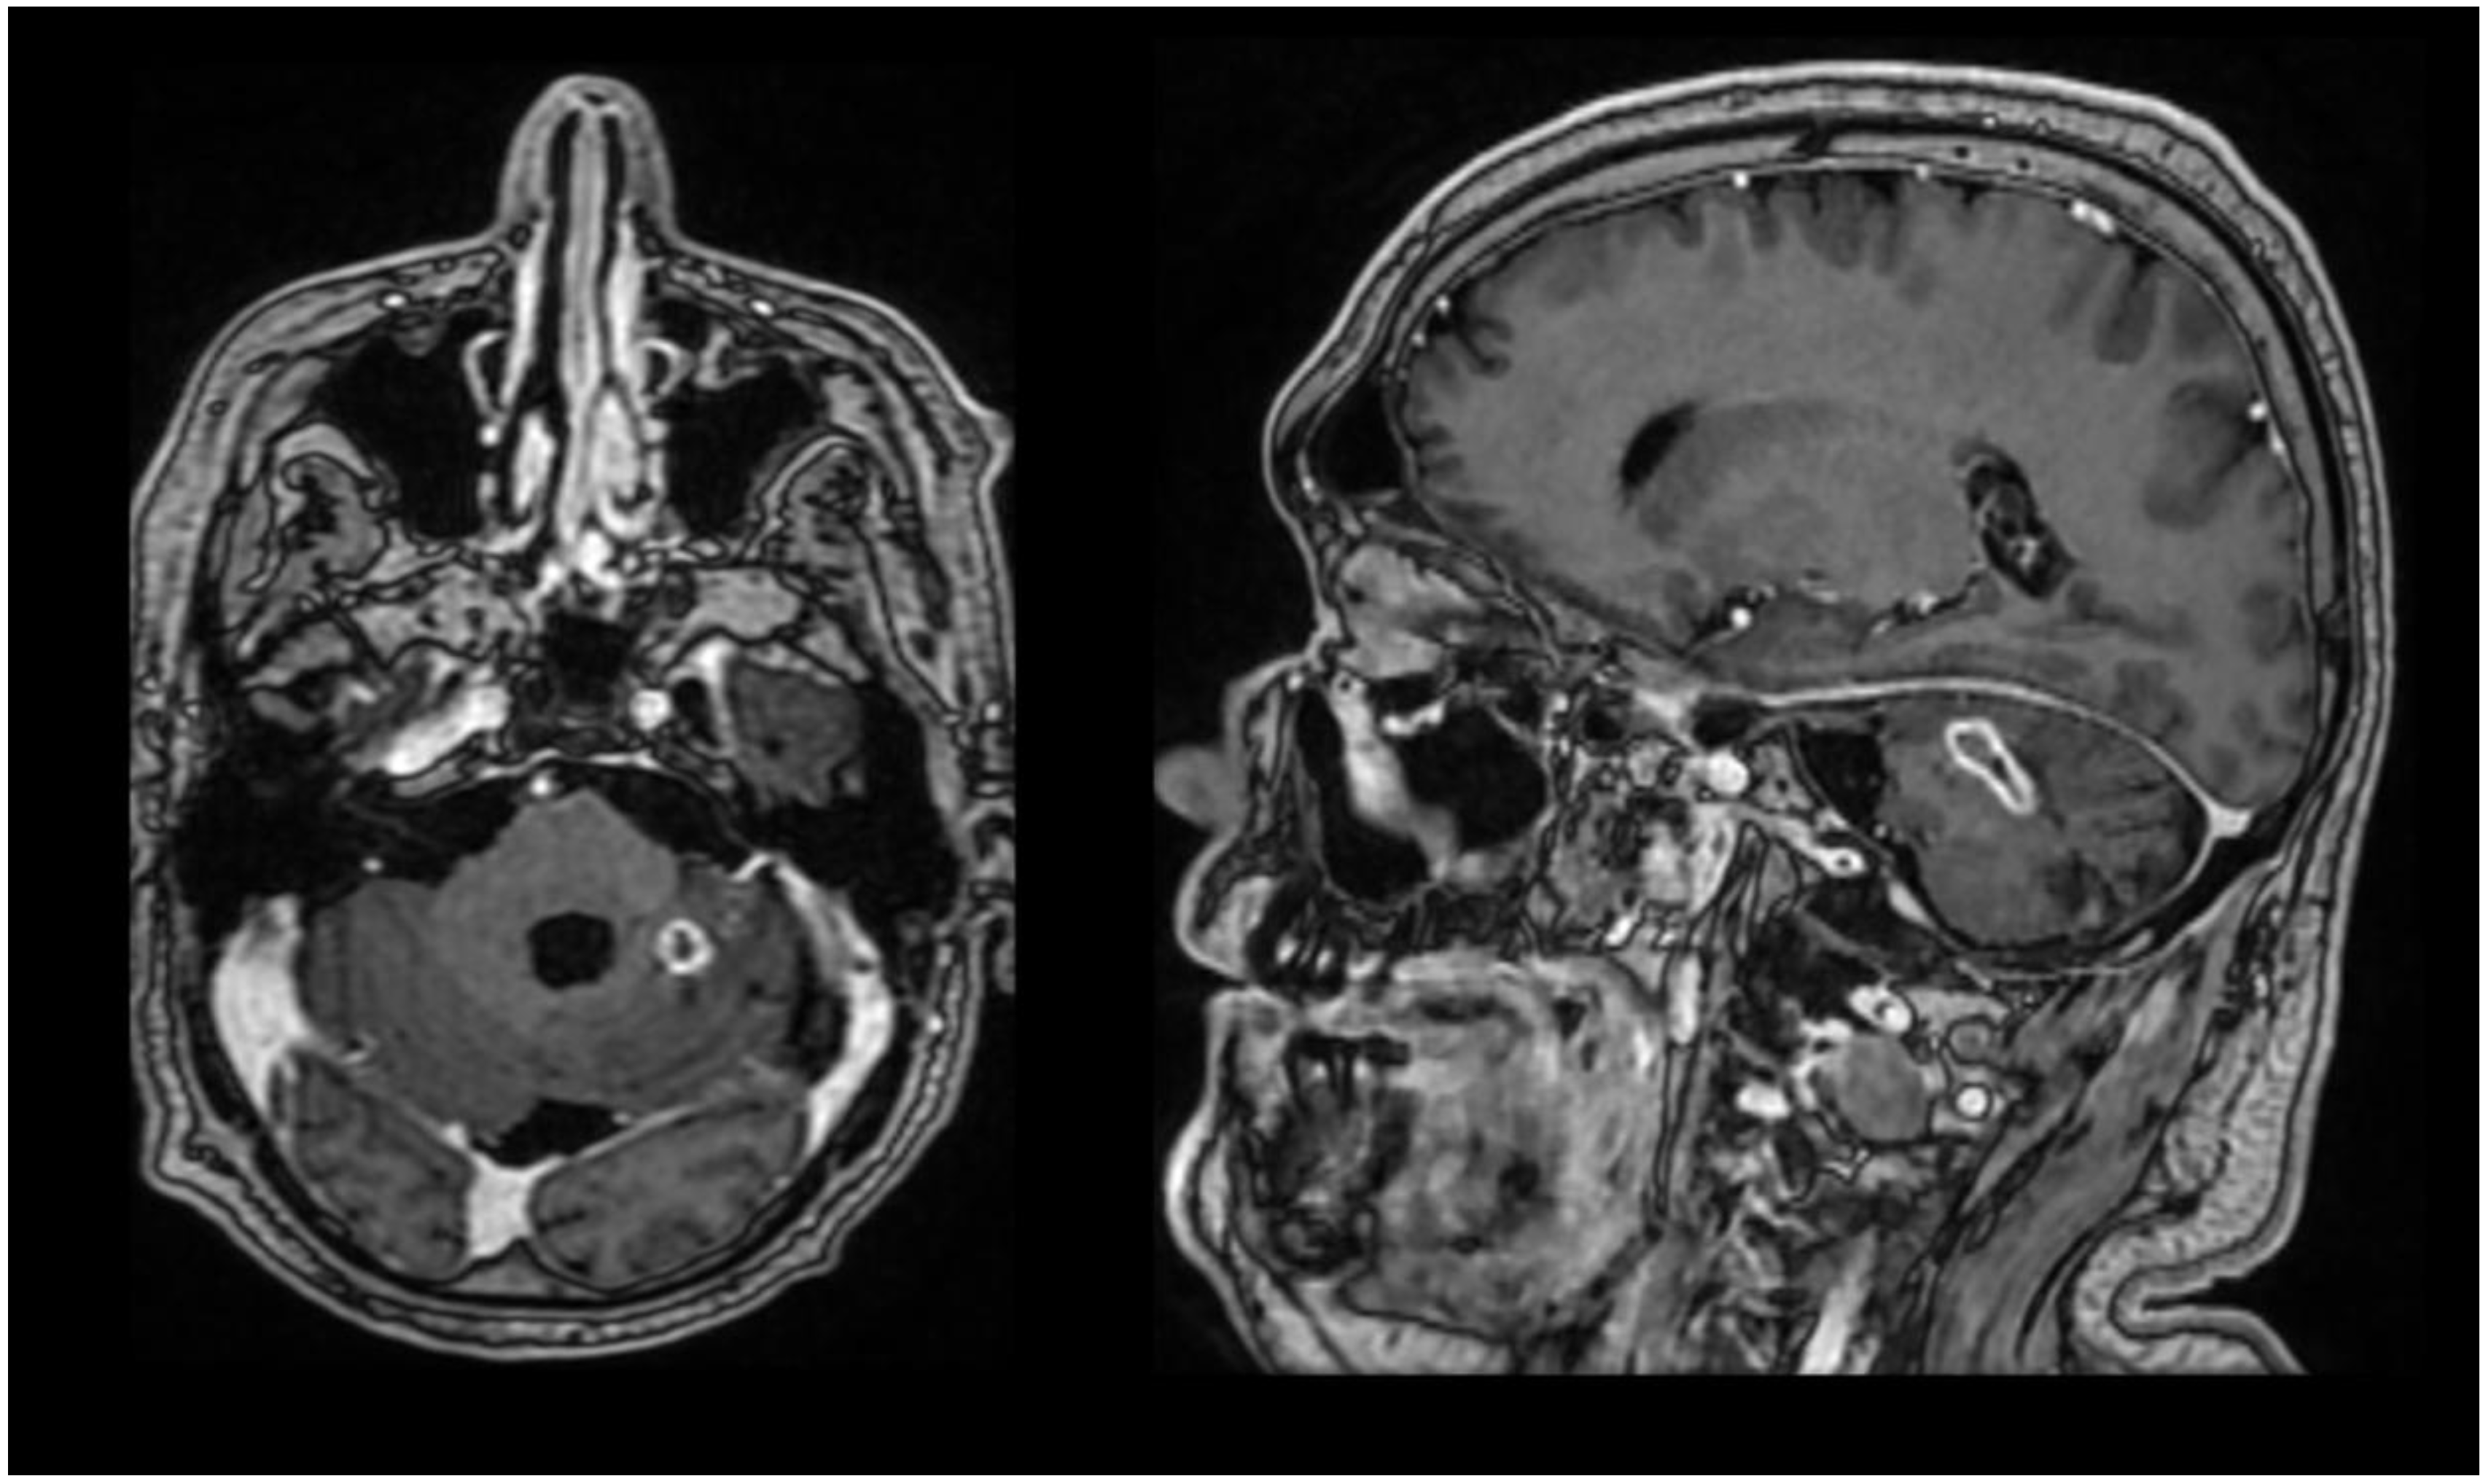

Dynamic follow-up included imaging studies and control lumbar punctures. Brain magnetic resonance imaging (MRI) at admission revealed findings consistent with occipital craniectomy, extensive postoperative occipital extracranial meningocele, a lesion in the left cerebellar hemisphere compatible with an abscess (25 × 10 mm), and chronic inflammatory changes of the bilateral maxillary sinuses (Figure 1).

Figure 1.

Brain MRI at admission in axial and sagittal section.